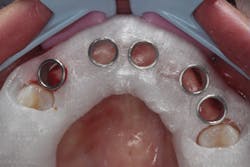

The patient was allowed to heal for three months before returning to uncover the implants. Full thickness flap incisions and retraction of Nos. 5–11 noted bone growth over the implants. We placed polyetheretherketone (PEEK) abutments over the implants to fabricate a fixed screw-retained provisional chairside (figure 9). We grafted once again with PRF, mineralized freeze-dried bone allograft, and fusion bone binder to thicken the area. One horizontal suture was placed from Nos. 7–10. One vertical mattress suture was placed around the No. 5 implant to obtain secondary healing, tucking the PRF membranes over the bone graft on the buccal and lingual tissue and keeping them exposed on the occlusal surface where the temps were screwed in (figure 10) . We allowed this to heal for two months before bringing the patient back to start the restorative phase of treatment (figure 11). During this time, the tissue was able to thicken with the added PRF and additional bone graft added around the implants.

Figure 9: PEEK abutments screwed into implants to convert to fixed temporaries